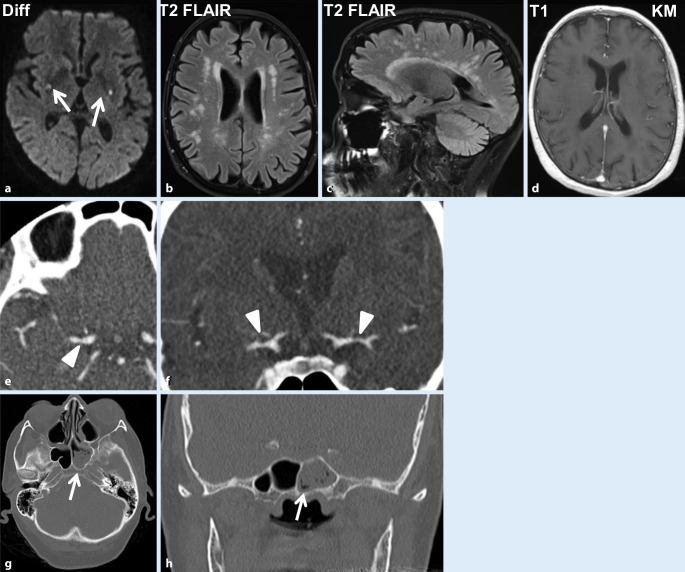

Klinisch-neurologisch stellte sich rasch nach stationärer Aufnahme ein Spontannystagmus nach rechts mit Drehschwindel ein, die Dysästhesien und Fußheberparesen zeigten sich unverändert. Im MRT des Schädels zeigten sich akute punktförmige lakunäre Ischämien in den Stammganglien beidseits sowie in der Medulla oblongata links in den diffusionsgewichteten Sequenzen. Ferner imponierten in den FLAIR-Aufnahmen bihemisphärische Marklagerläsionen, die kein Kontrastmittel aufnahmen (Abb. 1a–d). Die CT-Angiographie bestätigte bilaterale Gefäßkaliberschwankungen (Abb. 1e, f), die hochgradig verdächtig für eine intrazerebrale Vaskulitis waren. Die Neurographie konnte eine motorische axonale Neuropathie an beiden Nn. tibiales und peroneus objektivieren, die kalorische Testung eine Untererregbarkeit am rechten Ohr und die Tonaudiometrie eine Hochtonsenke rechts.

Bei der Suche nach einer Affektion der Atemwege zeigte sich in der CT der Nasennebenhöhlen eine Sinusitis ethmoidalis, maxillaris und sphenoidalis (Abb. 1g, h). Im Thoraxröntgenbild wurden Verschattungen gesehen, die sich in der Thorax-CT als bipulmonale multiple knotige Verdickungen bis 3 cm Durchmesser bestätigten. Eine Biopsie des Nasennebenhöhlenseptums erbrachte den Nachweis chronischer und akuter gefäßassoziierter Entzündungsinfiltrate. Epitheloidzellige Granulome oder eosinophile Zellen konnten jedoch nicht objektiviert werden. Auf eine erneute Biopsie wurde aufgrund der doch eindeutigen Befundkonstellation verzichtet.